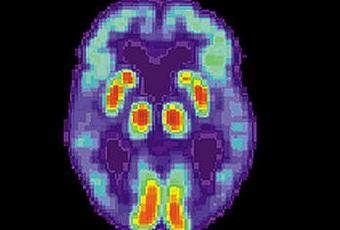

Image via WikipediaAfin de vous aider à reconnaître les signes précurseurs de la maladie, la Société Alzheimer a préparé la liste de symptômes suivante :- Pertes de mémoire qui nuisent aux activités quotidiennes